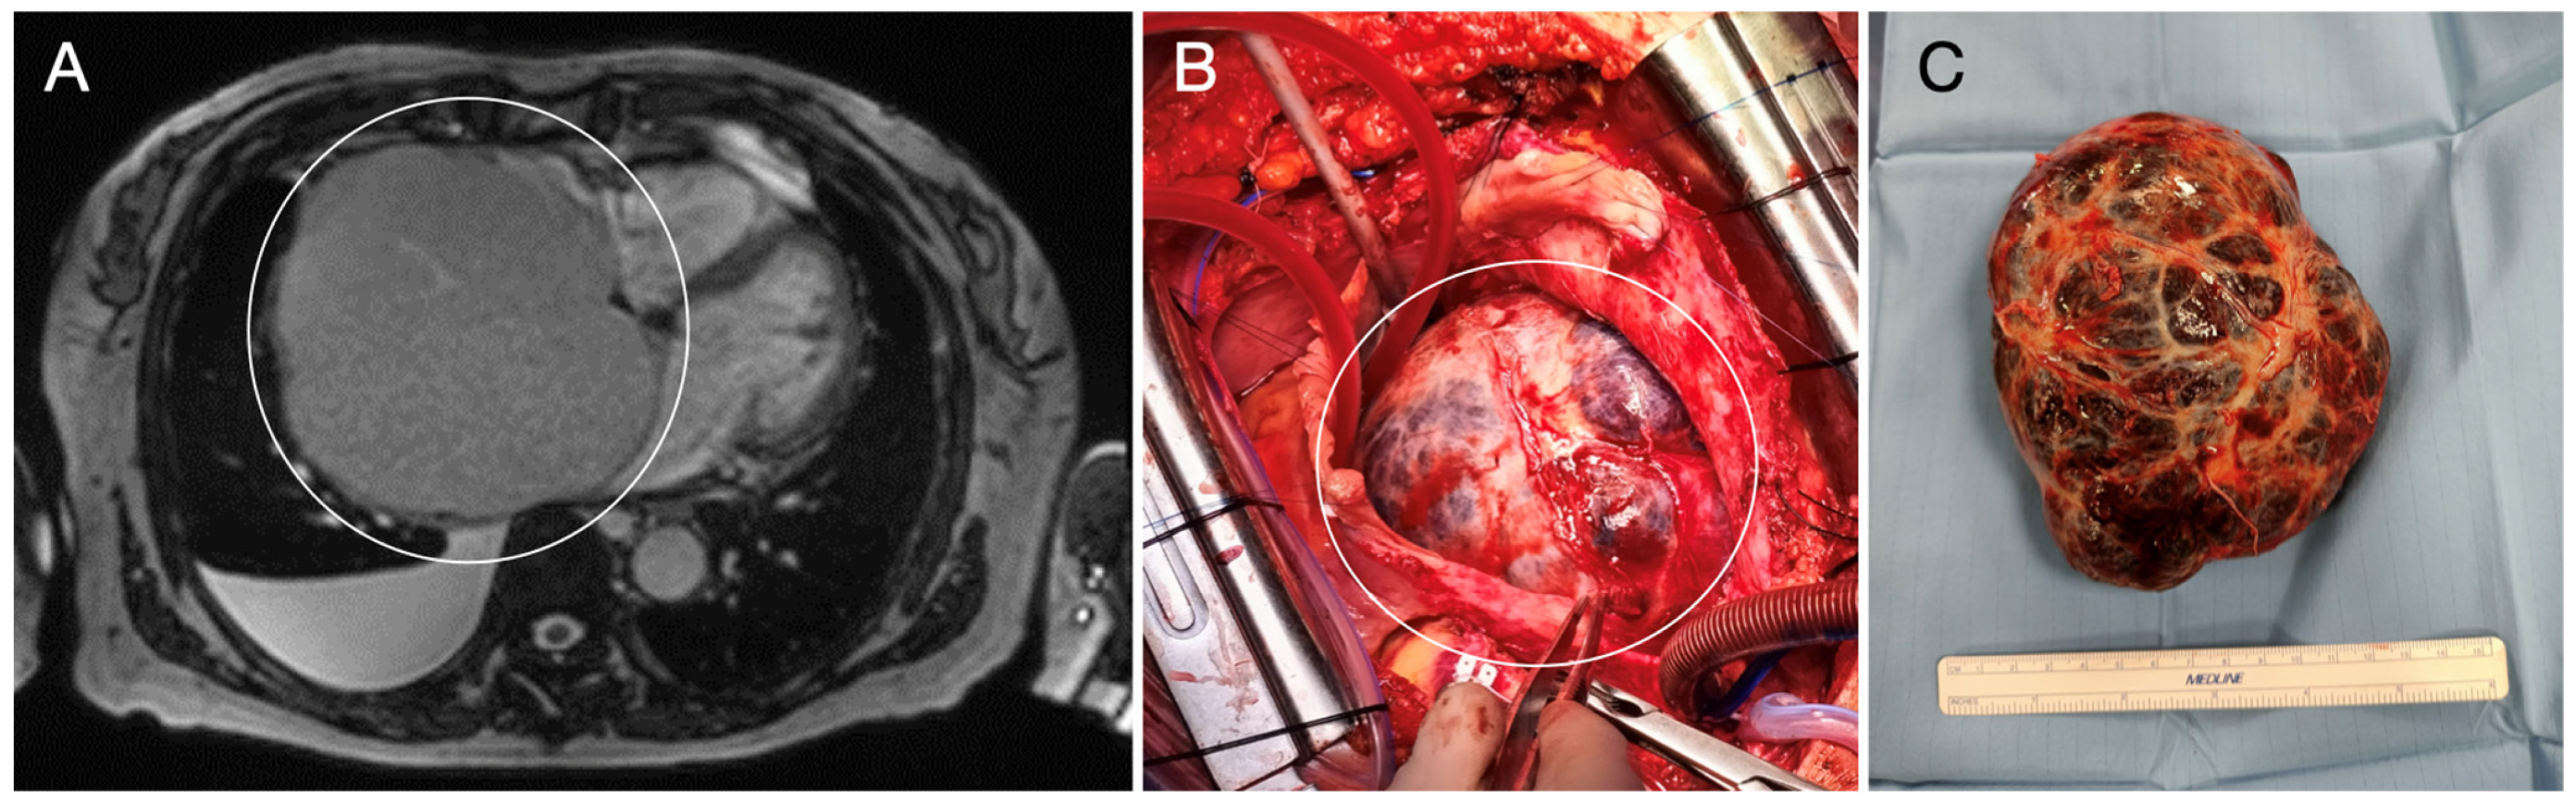

- Bianchi, G.; Ferrarini, M.; Matteucci, M.; Monteleone, A.; Aquaro, G.D.; Passino, C.; Pucci, A.; Glauber, M. Giant solitary fibrous tumor of the epicardium causing reversible heart failure. Ann. Thorac. Surg. 2013, 96, e49–e51. [Google Scholar] [CrossRef] [PubMed]